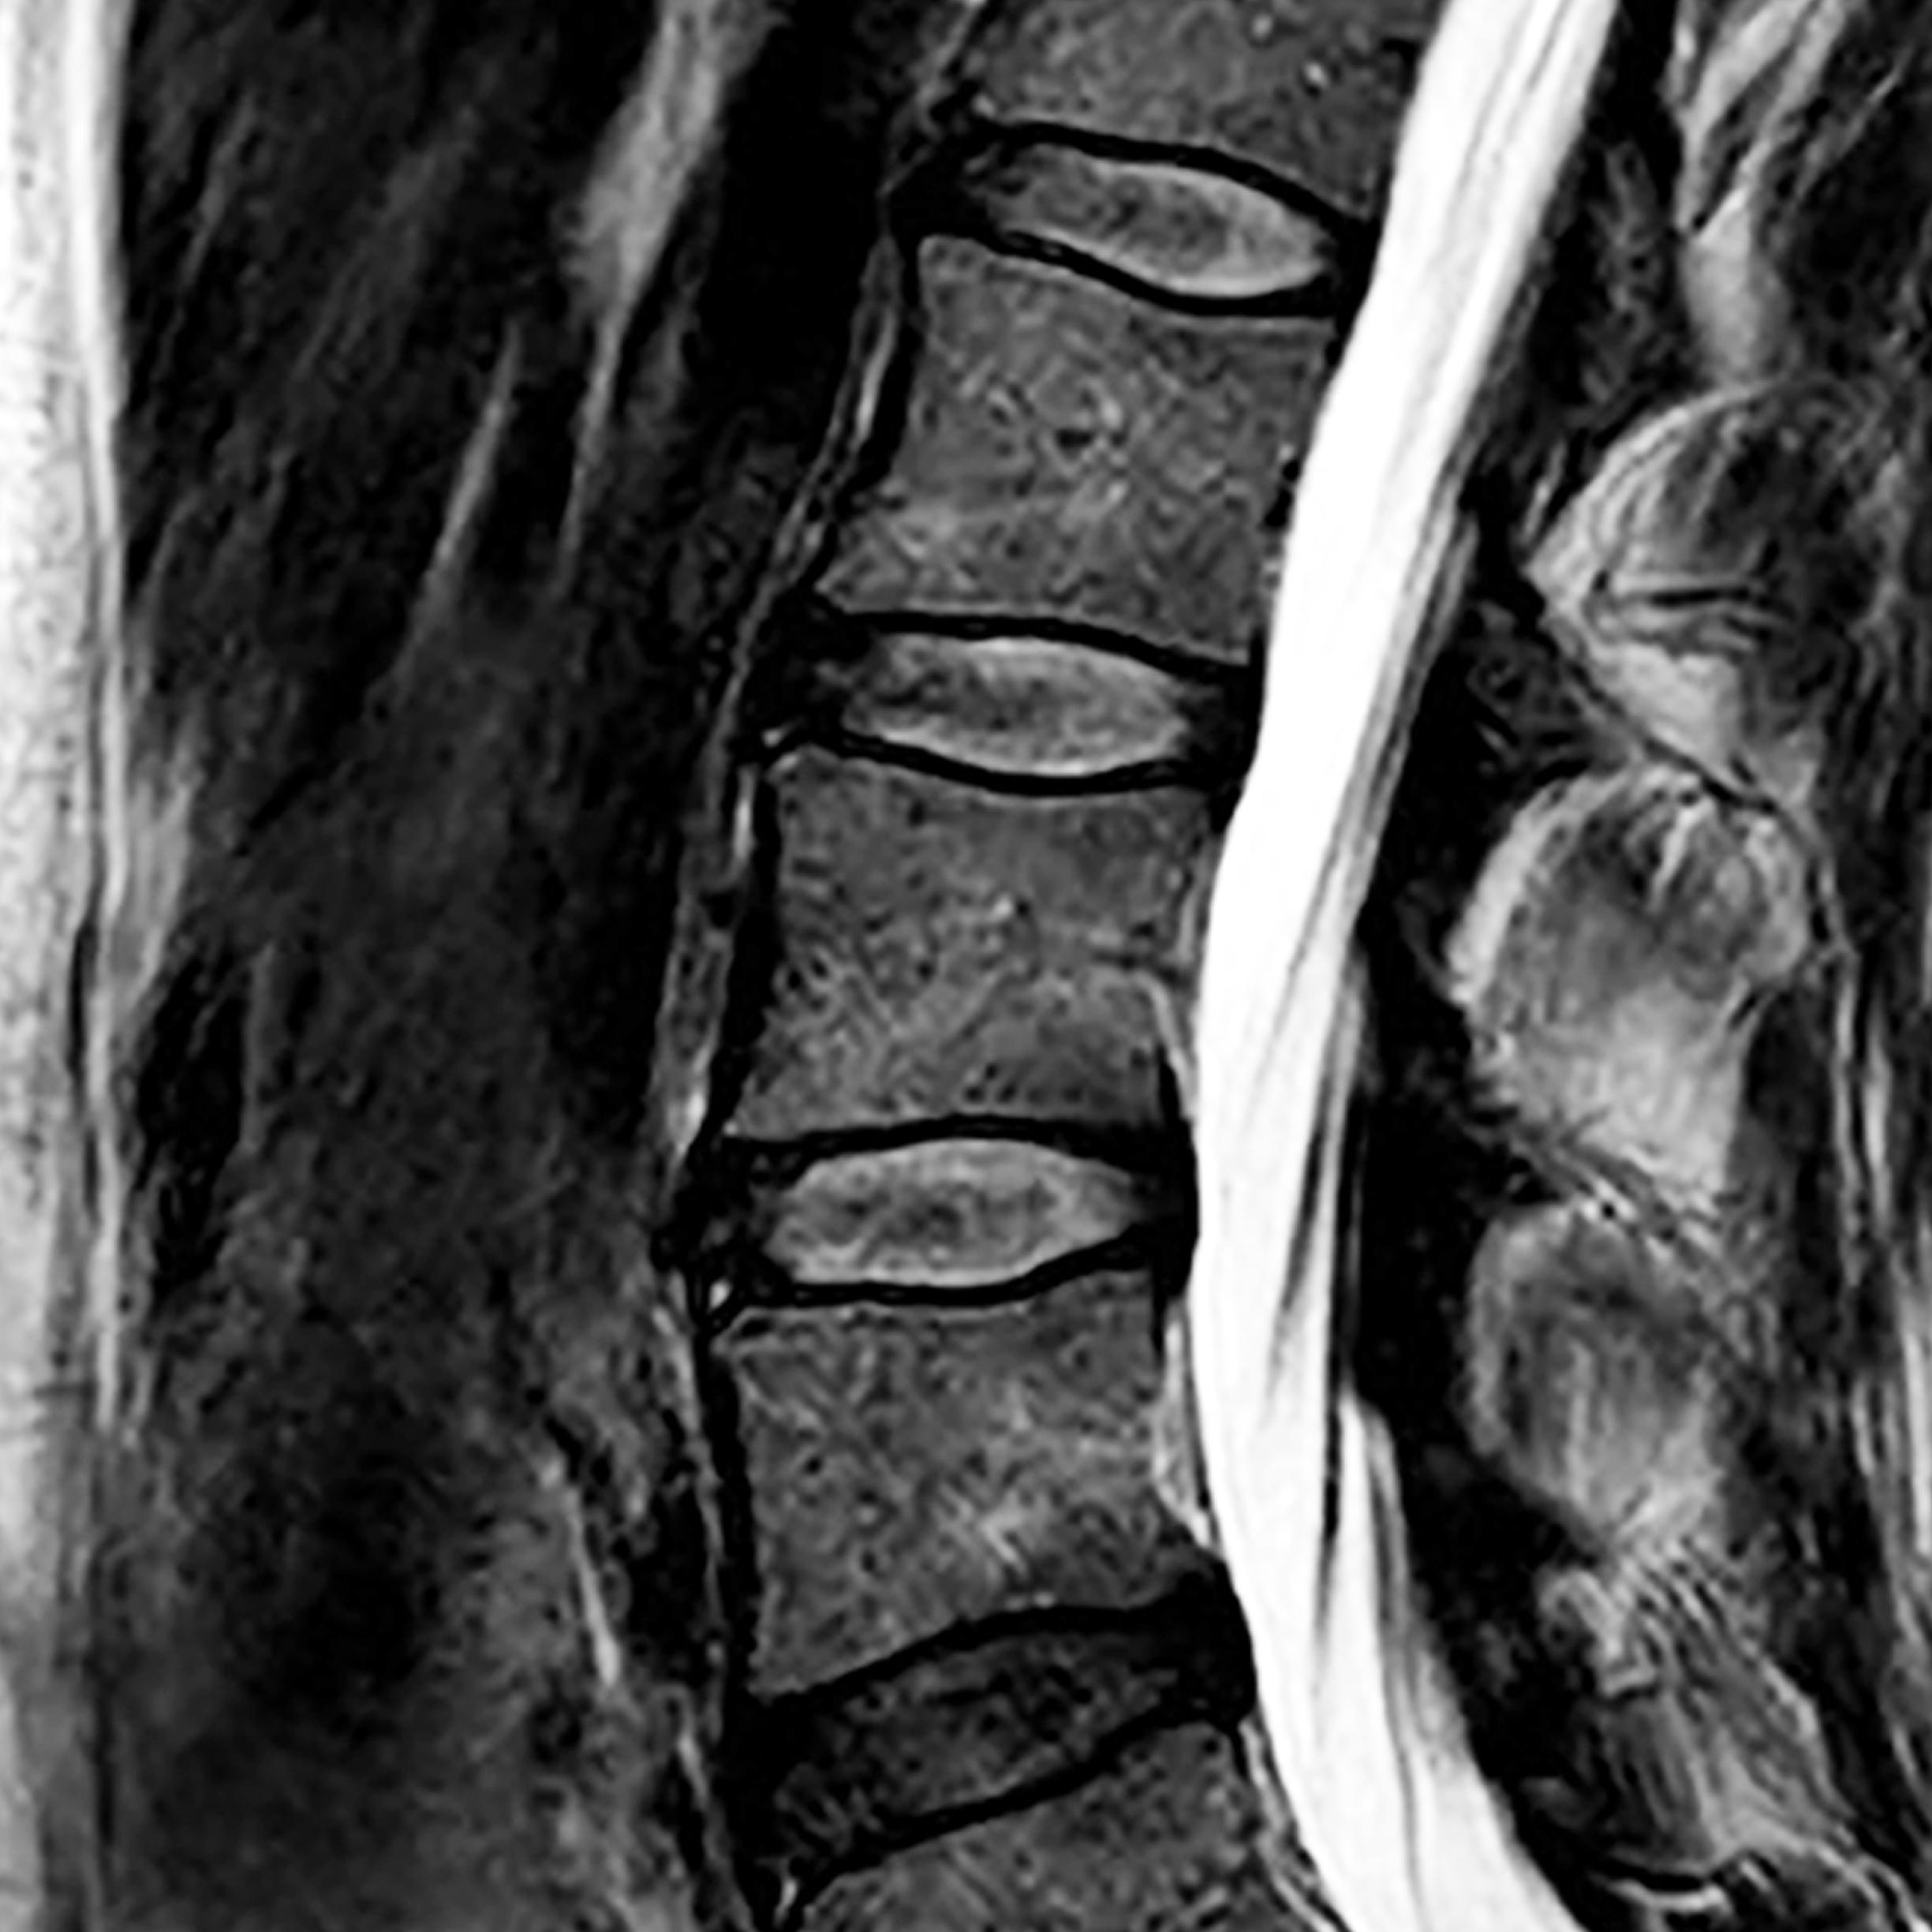

Ho pensato di presentare questo progetto attraverso un percorso di narrazione che si arricchisce progressivamente di contenuti e di presenze. Lo spazio maggiormente coinvolto è la vetrina di Mesia Space dove verrà proiettato inizialmente il lungometraggio omonimo Stone, un video della durata di circa 5 ore. In seguito, sempre all’interno della vetrina, il video sarà sostituito da un’installazione tridimensionale costituita da un gruppo di immagini della risonanza magnetica della mia colonna vertebrale, stampate su un tessuto di nylon semitrasparente. L’installazione nella vetrina rimarrà per tutta la durata del mio intervento a Mesia. La performance invece si svolgerà nello studio adiacente e consiste in un incontro di psicoterapia, di circa 50 minuti. Una psicoterapeuta si occuperà del mio vissuto, condividendo con me un ulteriore percorso di cura ampliato dalla funzione di testimonianza dei presenti. La seduta sarà documentata da un video che sarà proiettato il giorno del finissage.